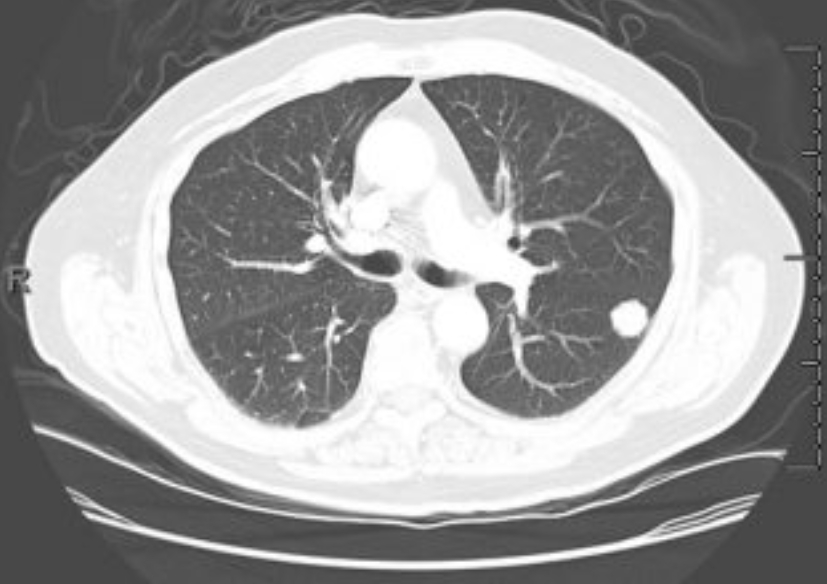

이 검사는 X선을 여러 각도에서 투사해 가슴 속을 단면으로 나누고, 컴퓨터가 이를 조합해 입체적으로 보여줍니다. 흉부ct로 볼수있는 질환 폐, 기관지, 심장, 혈관, 흉막, 림프절, 늑골까지 모두 관찰할 수 있어요. 몸을 절개하지 않고 내부를 볼 수 있으니 환자에게 부담이 적습니다. 조영제(혈관이나 염증 부위를 선명하게 보여주는 약물)를 사용하는 경우에는 정맥으로 주입하기도 하지만, 대부분은 통증이 거의 없습니다.

흉부CT는 이야기가 달라요. 얇게 자른 단면을 수백 장 촬영하기 때문에, 작은 병변도 놓치지 않습니다. 마치 산 전체를 한 장의 사진으로 보는 엑스레이와 달리, CT는 나무 한 그루 한 그루를 자세히 보는 느낌이에요. 예전에 병원에서 일했던 친구 말로는, 엑스레이에 아무 이상이 없던 환자가 CT에서 폐암 초기 진단을 받은 경우도 많았다고 합니다. 그만큼 CT는 정밀한 탐색 도구입니다.

흉부ct로 볼수있는 질환 폐질환뿐 아니라 심장과 혈관, 흉막, 림프절, 뼈 구조까지 한 번에 보여줍니다. 폐렴, 결핵, 폐기종, 기관지확장증, 간질성 폐질환 같은 호흡기 질환은 기본이고, 폐에 생긴 작은 결절이나 혹도 세밀하게 확인할 수 있습니다. 폐암이나 전이암처럼 초기에 증상이 거의 없는 병은 CT로 발견되는 경우가 많아요.

흉부CT는 병이 있는지 없는지를 넘어서, 병의 진행 정도와 주변 장기 침범 여부까지 보여줍니다. 예를 들어 폐암의 경우, 5mm 미만의 아주 작은 결절까지 찾아내고, 종양이 혈관이나 기관지에 닿았는지도 확인합니다. 초기에 잡아내면 완치율이 크게 높아지죠.

| 종양·암 | 폐암, 기관지암, 흉막종양 | 작은 결절(혹)도 5mm 이하까지 확인 가능하며, 조기 진단에 도움을 줍니다. |

Q8. 흉부CT 결과에서 ‘폐결절’이 나왔다는 말은 뭔가요?

A. 흉부ct로 볼수있는 질환 폐결절은 말 그대로 폐 안에 작은 혹이 있다는 뜻입니다. 대부분 양성(암이 아님)이고, 오래된 염증이나 석회화에 의한 것일 수도 있습니다. 그러나 결절의 크기가 8mm 이상이거나, 형태가 불규칙한 경우에는 추가 검사가 필요합니다. 영상의학과에서는 결절의 밀도, 경계, 주변 변화 등을 세밀하게 분석해 암 가능성을 판단합니다.